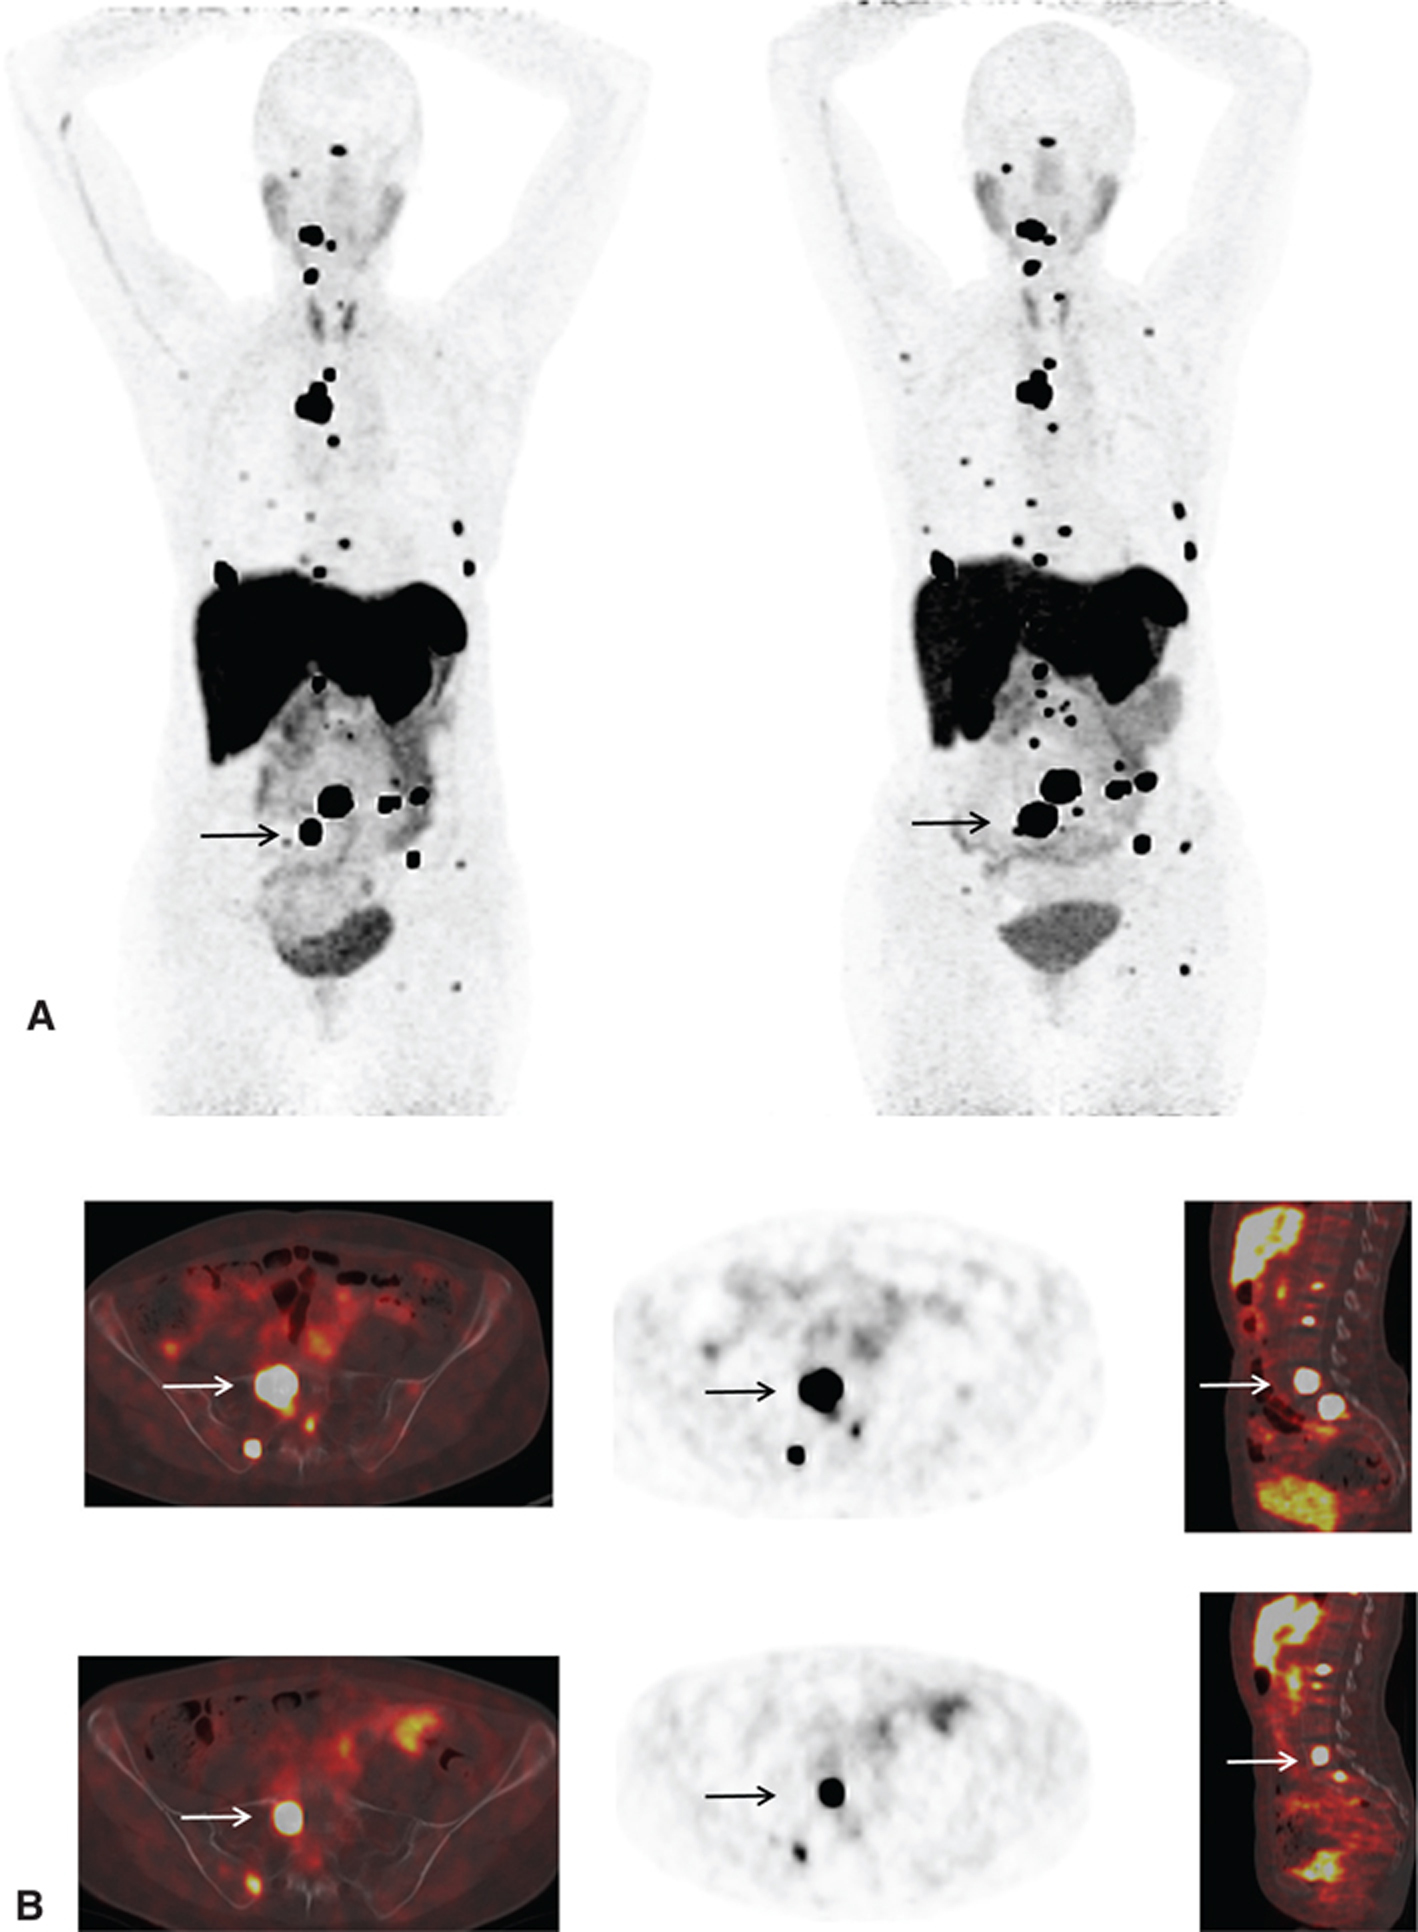

Ga-68 DOTATATE, with affinity to SSTR 2 and 5, was approved for use by the FDA in June 2016 (NETSPOT®).68 Ga-DOTATATE is indicated for localization of SSTR-positive NETs in both adults and children. Typical normal biodistribution is uptake in the pituitary, thyroid, adrenals, liver, spleen, uncinate process of pancreas, kidneys, and bladder. The method of evaluation is similar to octreoscan. Focal increased activity, not typical of normal distribution, is suspicious for disease (Figures 8 and 9). Similar to In-111 pentetreotide, false-positive findings can be seen and misinterpreted, and it is important to be aware of normal distribution and variants. No set diagnostic criteria currently exist for DOTATATE imaging, although there has been a proposal to standardize the reporting criteria using a 5-point structured system (54).

Fig 9

Figure 9 A 55-year-old woman with metastatic paraganglioma having an initial Ki67 proliferation index of 25% and strong SSTR2A immunostain but without SDHB mutation on germline testing. (A) Ga-68 DOTATATE PET/CT maximum intensity projection (MIP) images of the skull vertex to the proximal thigh on the left show widespread somatostatin receptor-positive metastatic disease, with progressive disease on the right image with enlarging pelvic osseous lesions (arrows). (B) Ga-68 DOTATATE PET/CT axial fused PET/CT, axial PET, and sagittal fused PET/CT images show enlarging vertebral lesion (arrows) on the current study (top images) as compared to the prior (bottom images).